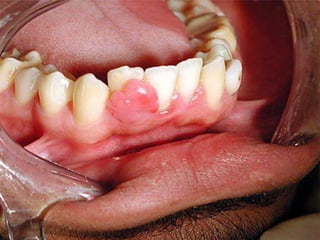

Peripheral Odontogenic Fibroma

 A peripheral odontogenic fibroma manifests as a

firm, slowly growing, sessile, and nodular growth of

the gingiva, most often on the mandibular buccal or

labial aspect as depicted below.

Peripheral Odontogenic Fibroma to arise from odontogenic epithelial rests in the periodontal ligament or the attached gingiva itself.  The entity, formerly confused with peripheral cemento-ossifying fibroma, is considered to be the extraosseous counterpart of the central odontogenic fibroma of the World Health Organization type.  A peripheral odontogenic fibroma manifests as a firm, slowly growing, sessile, and nodular growth of the gingiva, most often on the mandibular buccal or labial aspect as depicted below.  wide age range and affects both sexes equally.